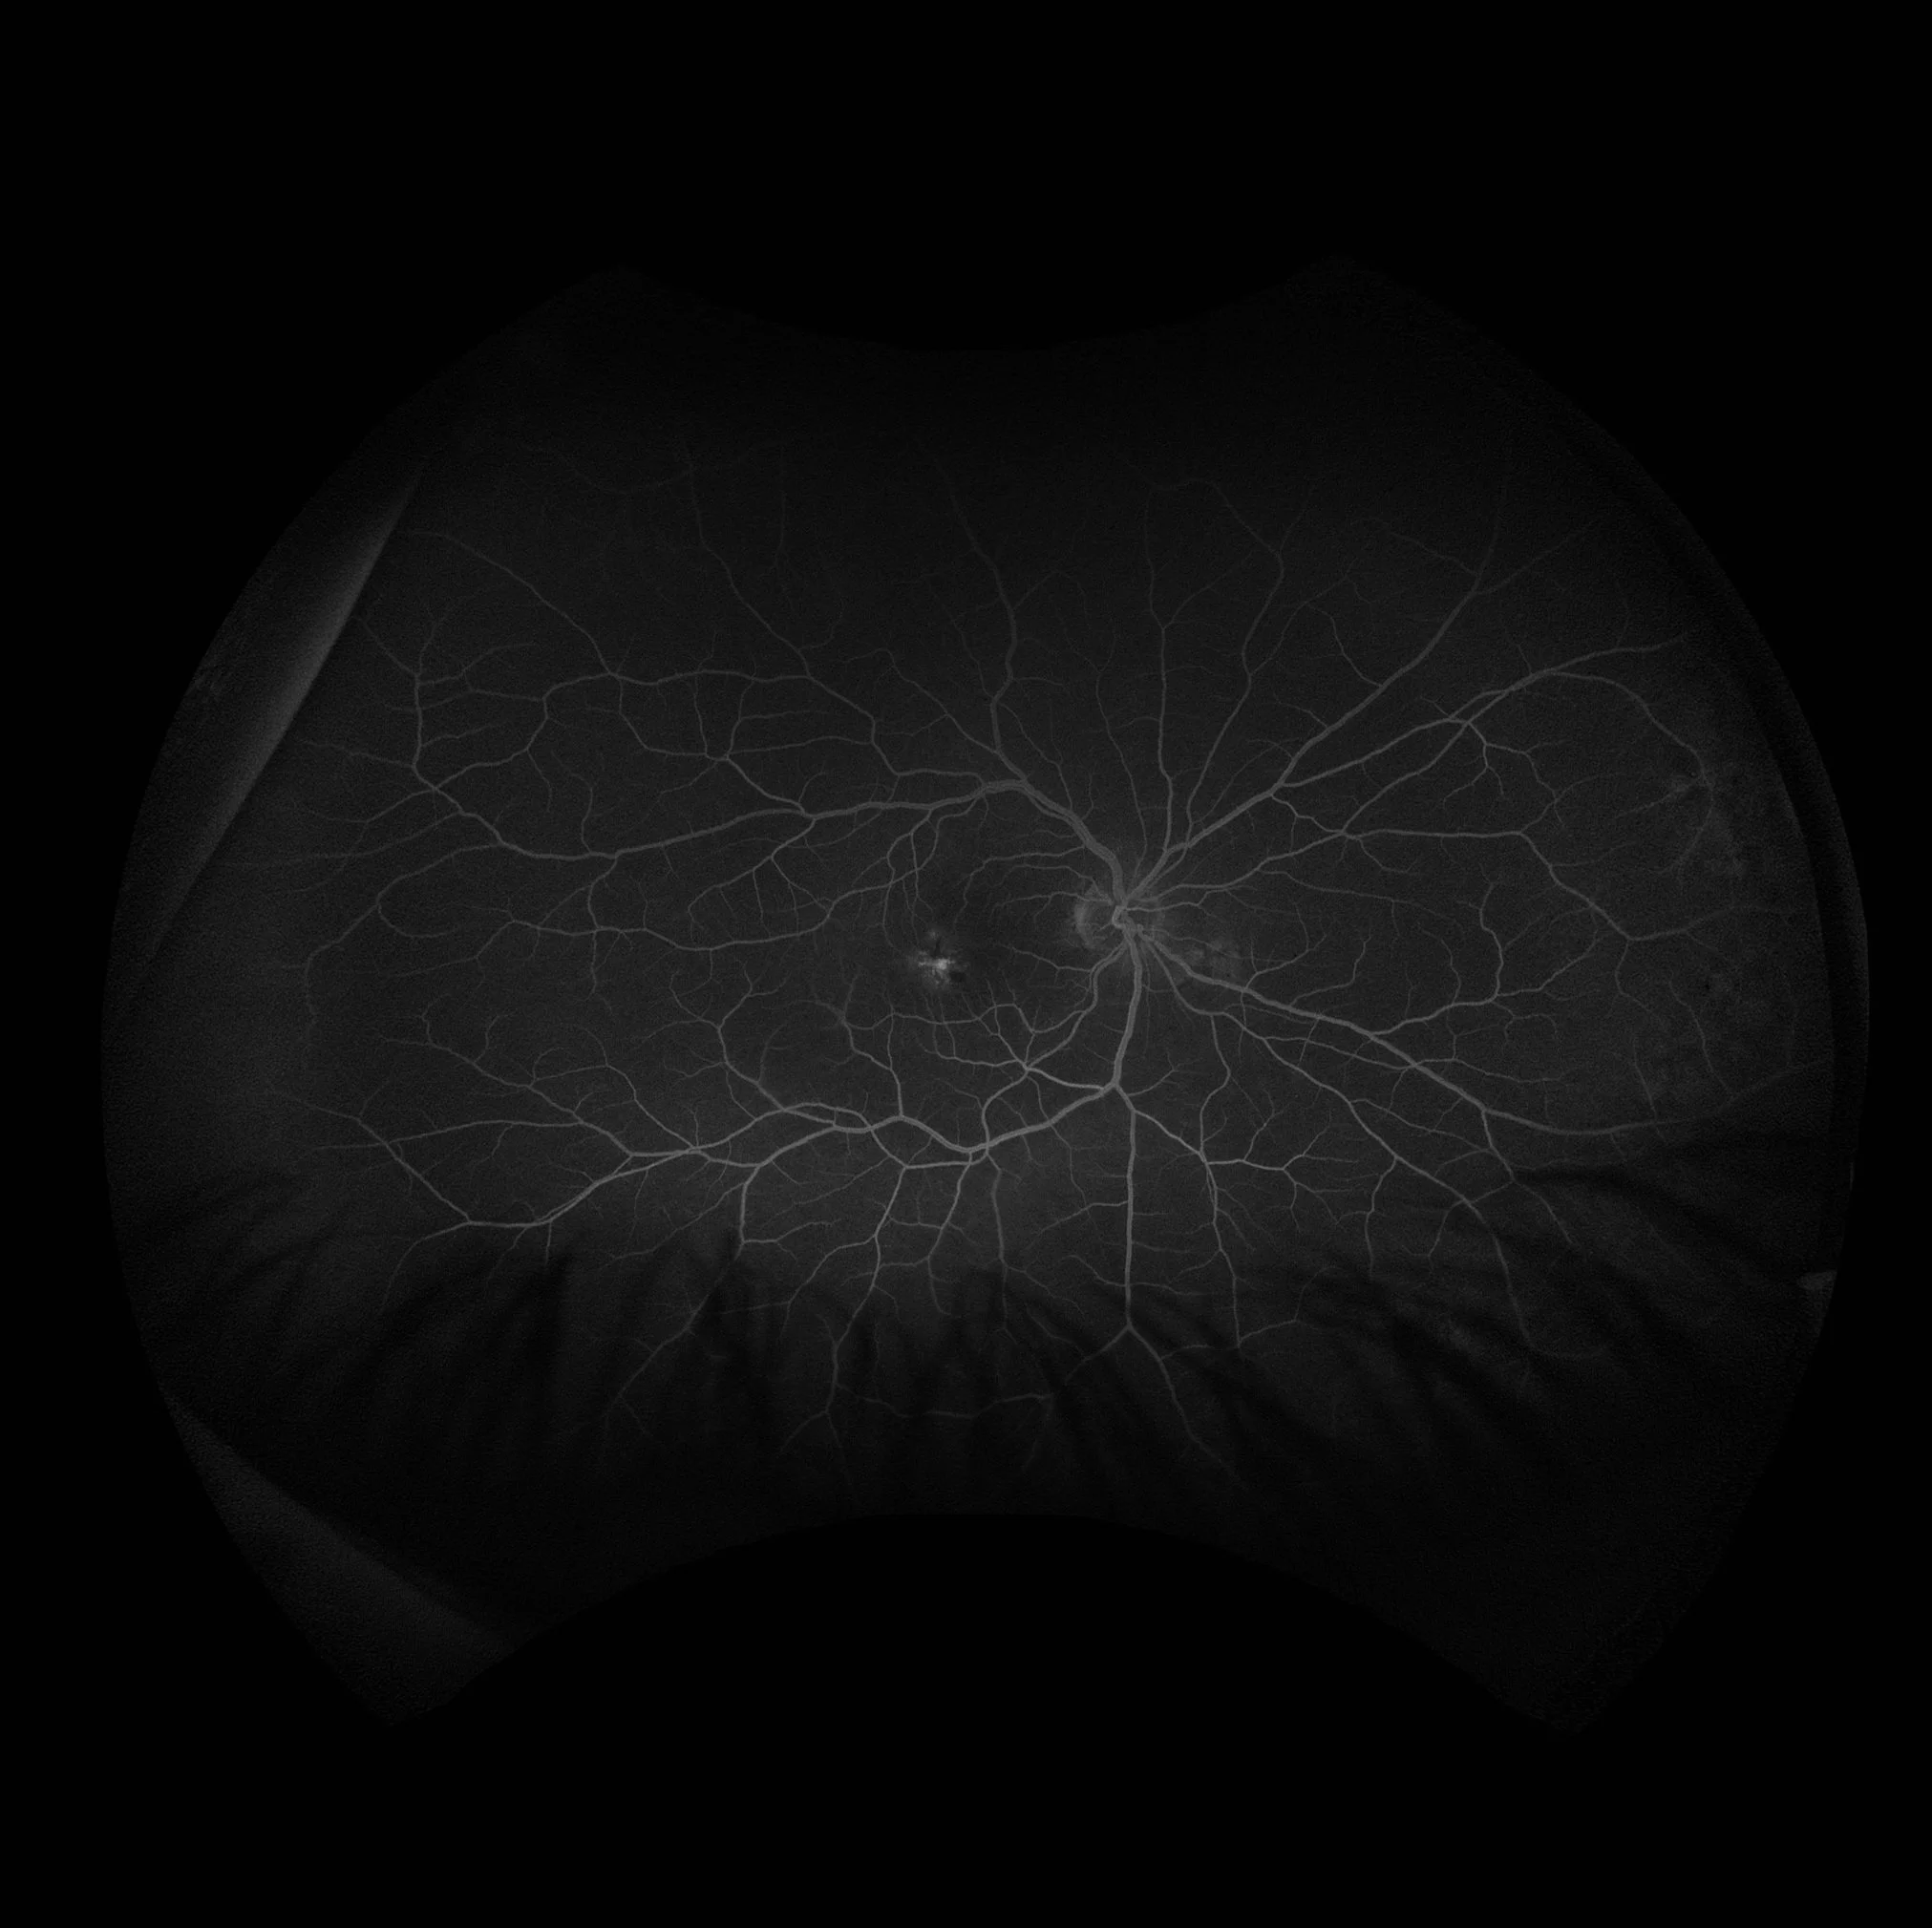

• Late Leakage at the Macula

A leak occurs when there is loss of fluorescein into the extracellular space. A full leak begins early in the scan and increases in size and intensity with time. This photo shows late macular leakage and right angled vessels characteristics of macular talengiectasia.

• Cystoid appearance (inside the macula, aflower petal appearance because of the organization of the outer plexiform layer; outside of the macula, a honey- comb appearance): diabetic retinopathy, telangiectasis, choroidal or retinal inflammation, subretinal neovascularization, subretinal inflammation, choroidal tumours.